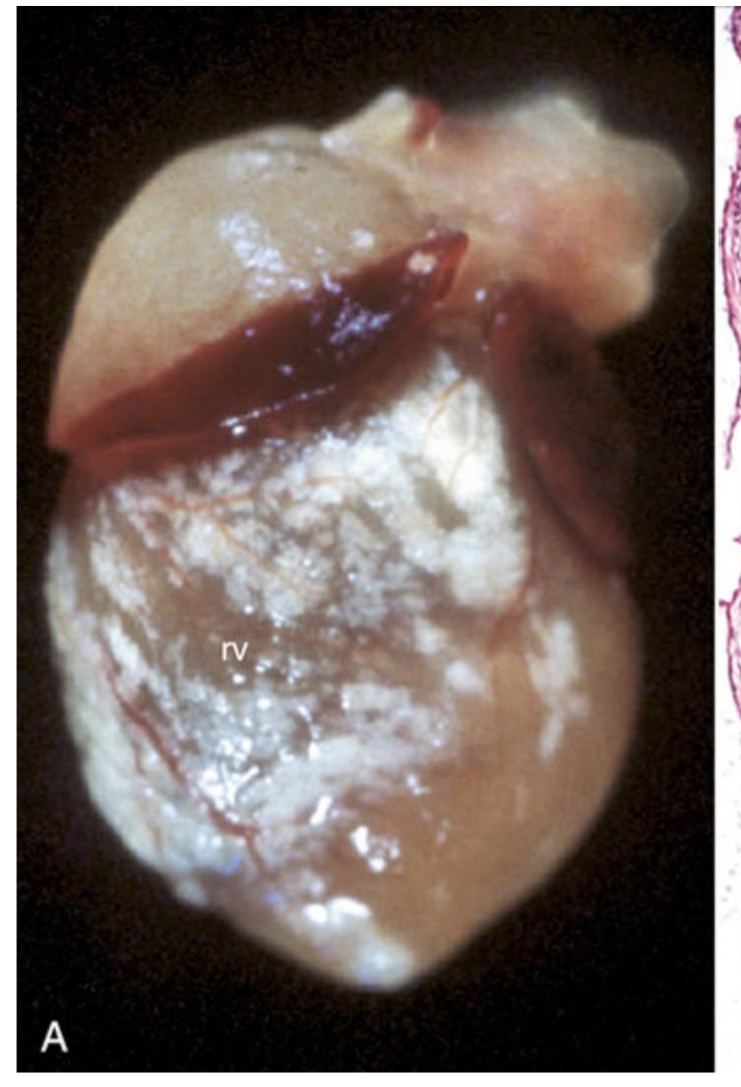

what is this showing?

epicardial mineralization → white deposits over the right ventricle